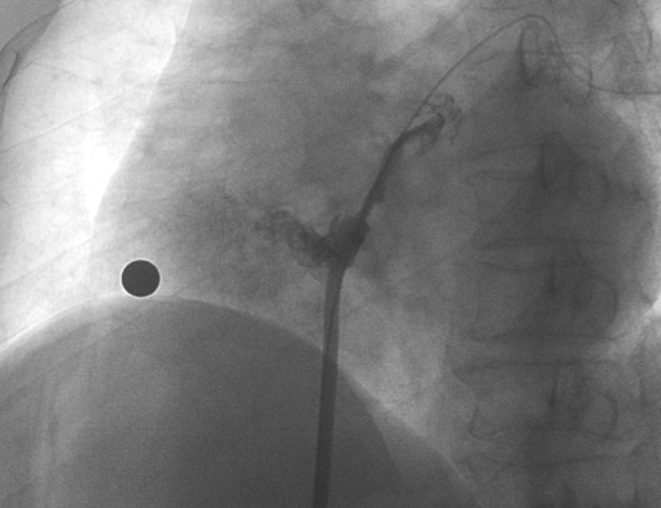

儲(chǔ)慧民教授團(tuán)隊(duì)為患者進(jìn)行經(jīng)皮卵圓孔未閉封堵術(shù)

在本次植入手術(shù)中,接受介入封堵術(shù)的是一名卵圓孔未閉(長隧道型)的患者。患者60歲,男性,7年前曾診斷腦梗死,此次因新發(fā)腦梗死入院,無房顫及頸動(dòng)脈狹窄;經(jīng)胸心臟超聲和心臟聲學(xué)造影檢查提示卵圓孔未閉,Valsalva動(dòng)作后心房水平大量右向左分流。經(jīng)儲(chǔ)慧民教授團(tuán)隊(duì)評(píng)估,結(jié)合相關(guān)病史并考慮PFO及不明原因卒中,遂決定對(duì)患者開展經(jīng)皮PFO封堵術(shù)。

術(shù)中造影顯示患者為PFO且長隧道型,目前市場上已商業(yè)化的PFO封堵器難以滿足該患者解剖結(jié)構(gòu)封堵需求。迪創(chuàng)醫(yī)療自主研發(fā)的OmniSeal PFO封堵器自適應(yīng)性雙盤貼合設(shè)計(jì)能廣泛適應(yīng)不同PFO隧道長度的解剖結(jié)構(gòu)和形態(tài),其雙盤外包覆式阻流和隧道內(nèi)填充阻流相結(jié)合的雙重阻流設(shè)計(jì),可為此患者實(shí)現(xiàn)有效封堵。與此同時(shí),OmniSeal首創(chuàng)的完全可穿刺式設(shè)計(jì),也為此患者最大程度地保留了房間隔區(qū)域穿刺通道,以實(shí)現(xiàn)全兼容未來可能的左心系統(tǒng)二次介入術(shù)。術(shù)終造影和心臟超聲顯示封堵完全、效果良好。作為OmniSeal的首例臨床應(yīng)用,本次手術(shù)的順利完成和優(yōu)異效果充分體現(xiàn)了產(chǎn)品的設(shè)計(jì)創(chuàng)新優(yōu)勢。

造影顯示長隧道型PFO